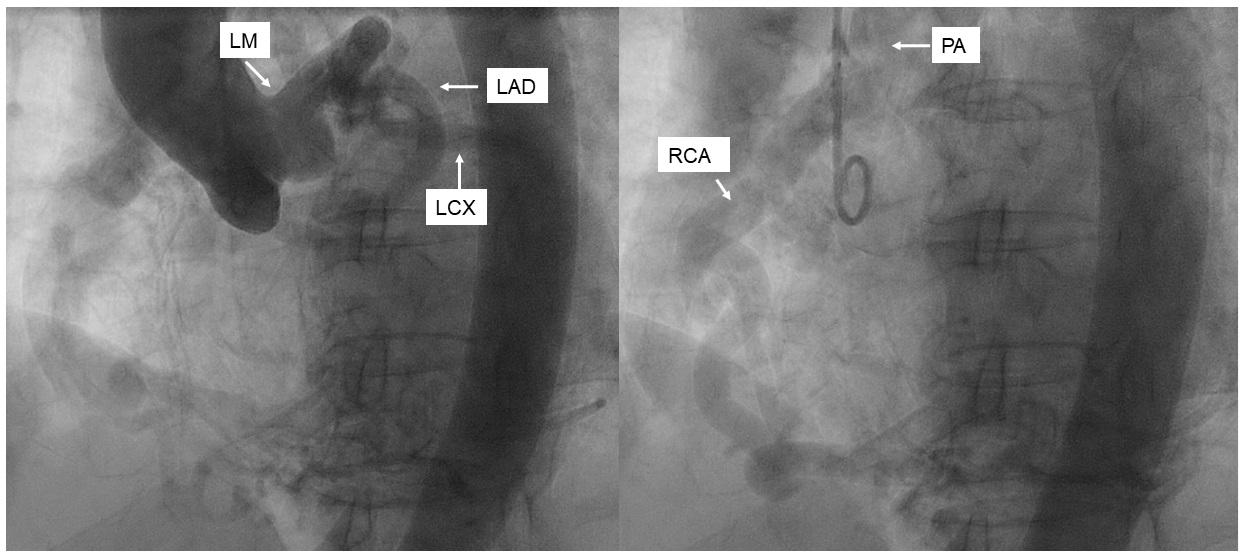

Selective left coronary angiography showed an ectatic left main artery and tortuous collaterals from the proximal left anterior descending (LAD) artery to a severely ectatic right RCA. The LAD was also severely ectatic and filled late. Retrograde filling of the pulmonary artery from the RCA was visualized (Figure 1, Video 1). We were unable to engage the RCA selectively with multiple diagnostic catheters. Ascending aortography confirmed absence of RCA ostium from the aorta and suggested the diagnosis of anomalous right coronary artery from pulmonary artery (ARCAPA) (Figure 2, Video 2). CT angiography confirmed ARCAPA with large left-to-right collaterals from LAD to RCA (Figures 3-5). There were no other congenital heart anomalies. Echocardiography showed normal biventricular function and normal chamber sizes. A myocardial perfusion Single Photon Emission Computed Tomography (SPECT) study showed a moderate intensity, medium-sized, partially reversible defect in the RCA distribution. The patient was referred to cardiothoracic surgery for consideration of reimplantation of the RCA to the aorta. However, due to her asymptomatic status at baseline, the decision was made to pursue initial conservative management.